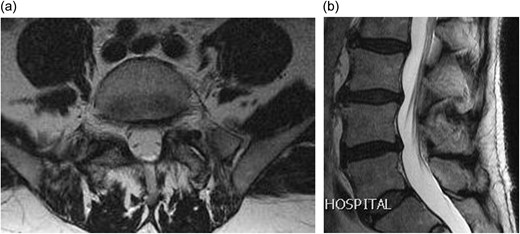

A 66-year-old male presented to our institution with 12 months history of severe back pain and left leg pain in L5/S1 distribution. On examination he had a normal neurology except for a dull left ankle jerk. Magnetic resonance imaging (MRI) of his lumbo-sacral spine showed a left L5/S1 synovial cyst (Fig. 1a and b). The findings and management options were discussed with the patient, who decided for a surgical option. However in view of his recent cardiac history it was decided to see him again in clinic in 6 months’ time. After reviewing him in clinic, he was added to the surgical waiting list and as his MRI scan was a year old, fresh set of scans was requested nearer to his operation date. Surprisingly his repeat MRI showed complete resolution of the L5/S1 synovial cyst (Fig. 2a and b).

(a) Axial T2 weighted MRI showing a left sided L5/S1 synovial cyst impinging on the left S1 nerve root; (b) sagittal T2 weighted MRI showing a L5/S1 synovial cyst.